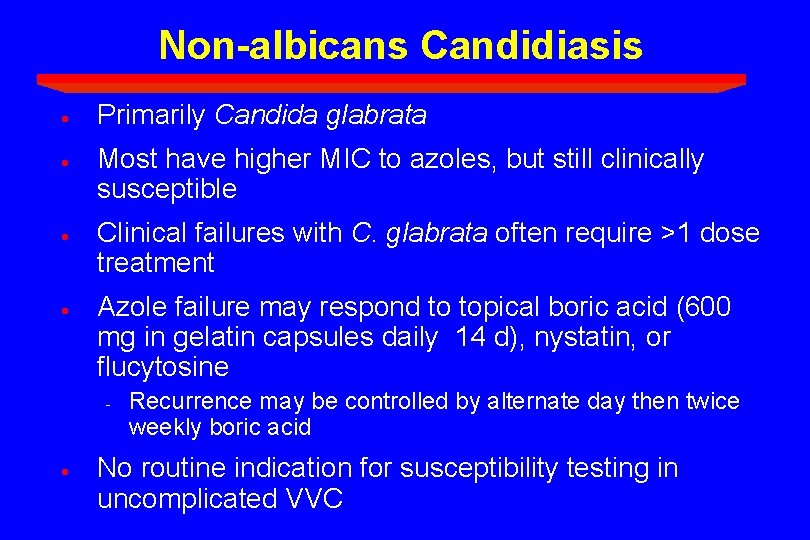

Non-albicans Candidiasis · Primarily Candida glabrata · Most have higher MIC to azoles, but still clinically susceptible · Clinical failures with C. glabrata often require >1 dose treatment · Azole failure may respond to topical boric acid (600 mg in gelatin capsules daily 14 d), nystatin, or flucytosine - · Recurrence may be controlled by alternate day then twice weekly boric acid No routine indication for susceptibility testing in uncomplicated VVC